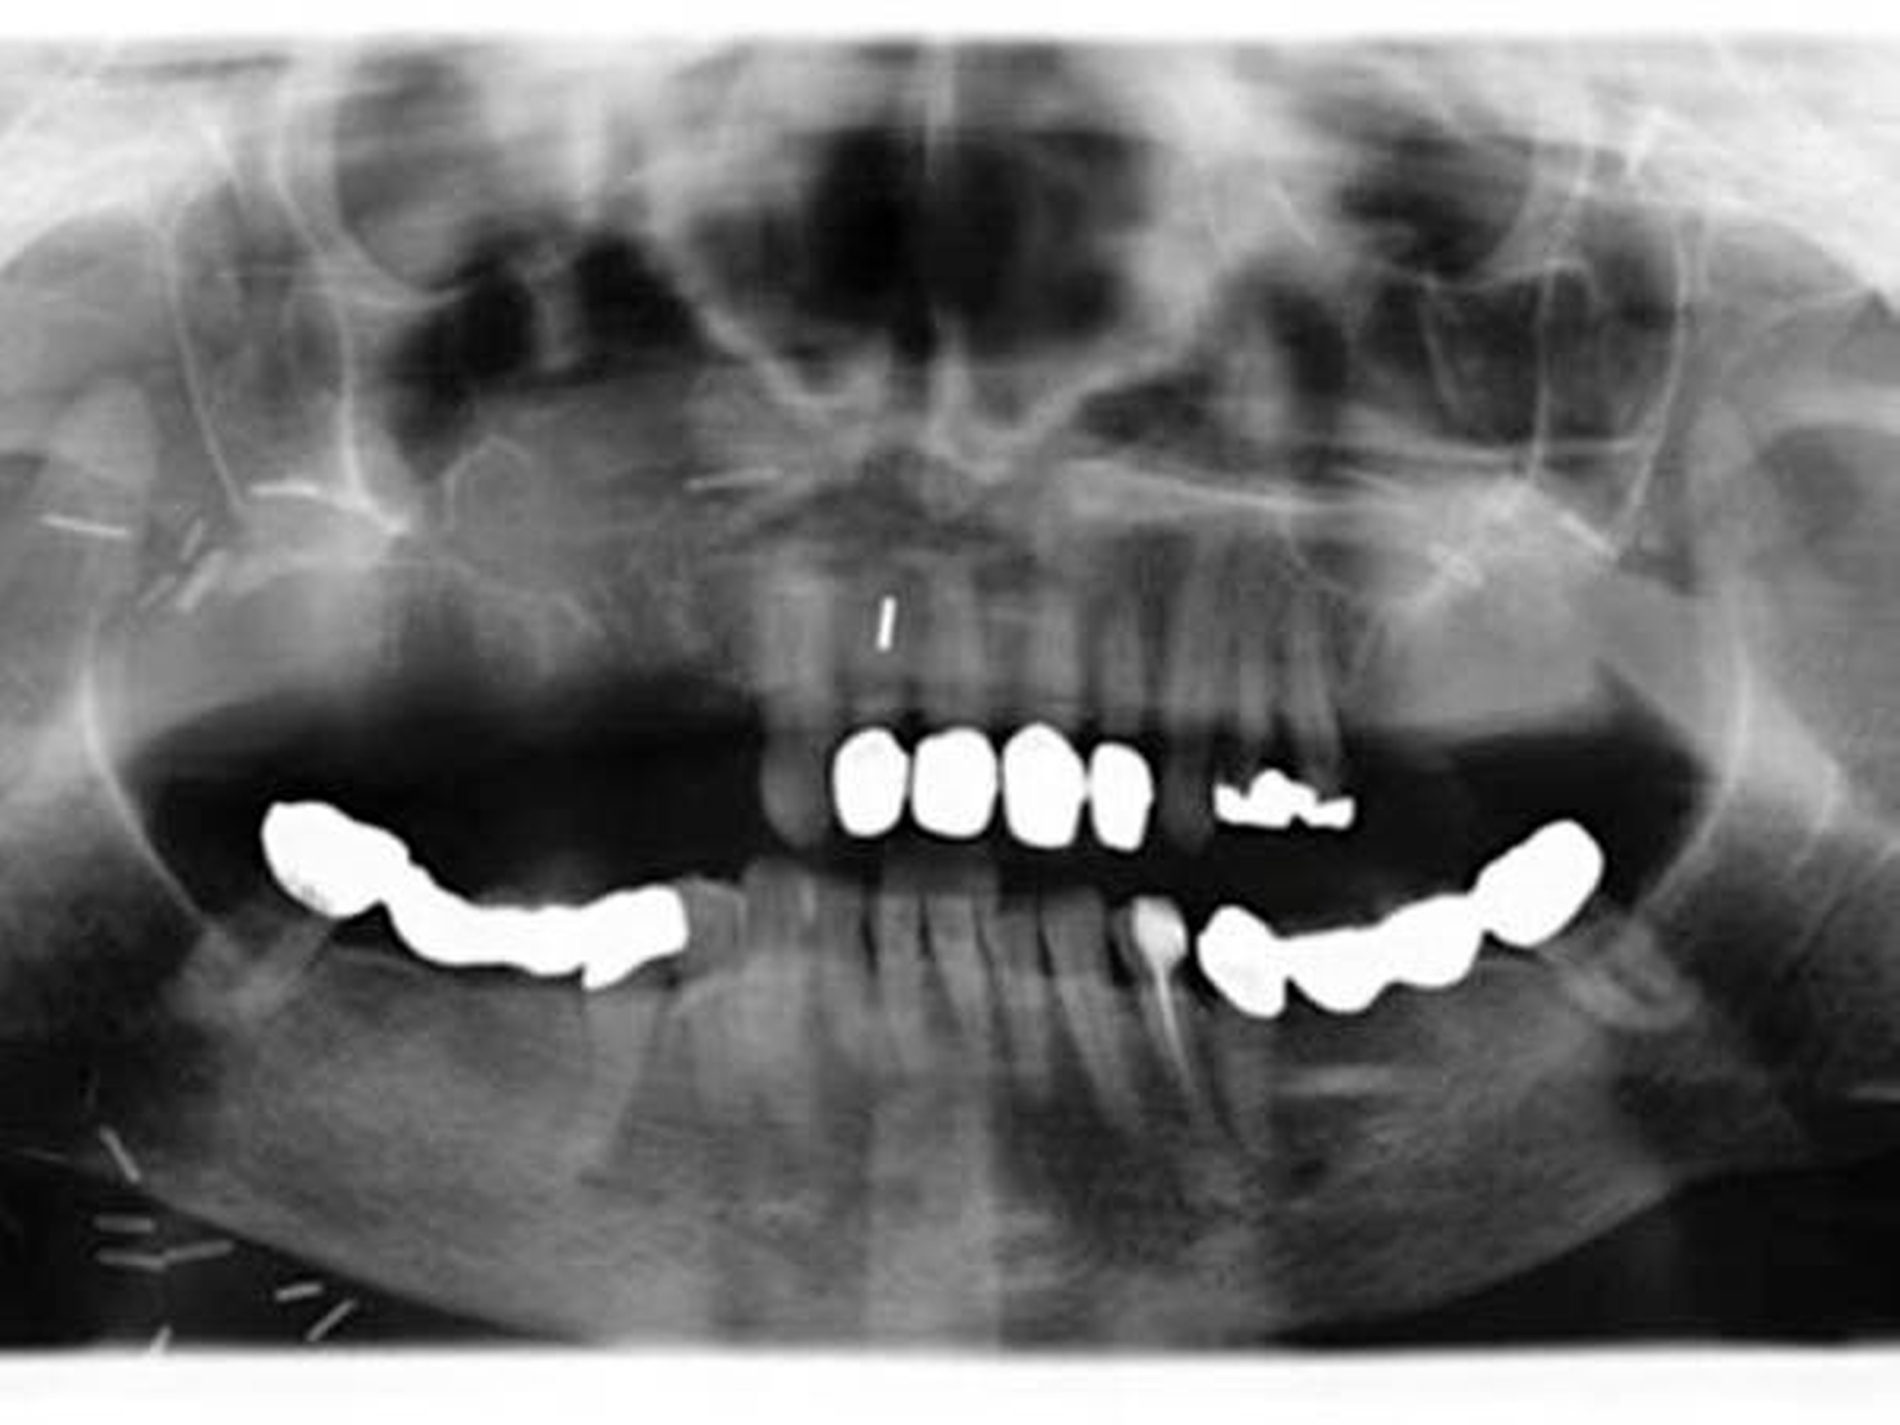

Der postoperative Verlauf der Patientin gestaltete sich problemlos. Die Trachealkanüle konnte nach Abschwellen am dritten postoperativen Tag entfernt werden. Schlucken und Sprechen waren sofort gut möglich. Das Lappentransplantat war zu jeder Zeit gut vaskularisiert und seine Grenzen dicht. Die Nasenatmung war nicht mehr gestört.

Die Patientin stellt sich regelmäßig und engmaschig in unserer Tumorsprechstunde zur Nachsorge vor, die regelmäßige klinische und radiologische Kontrollen umfasst.